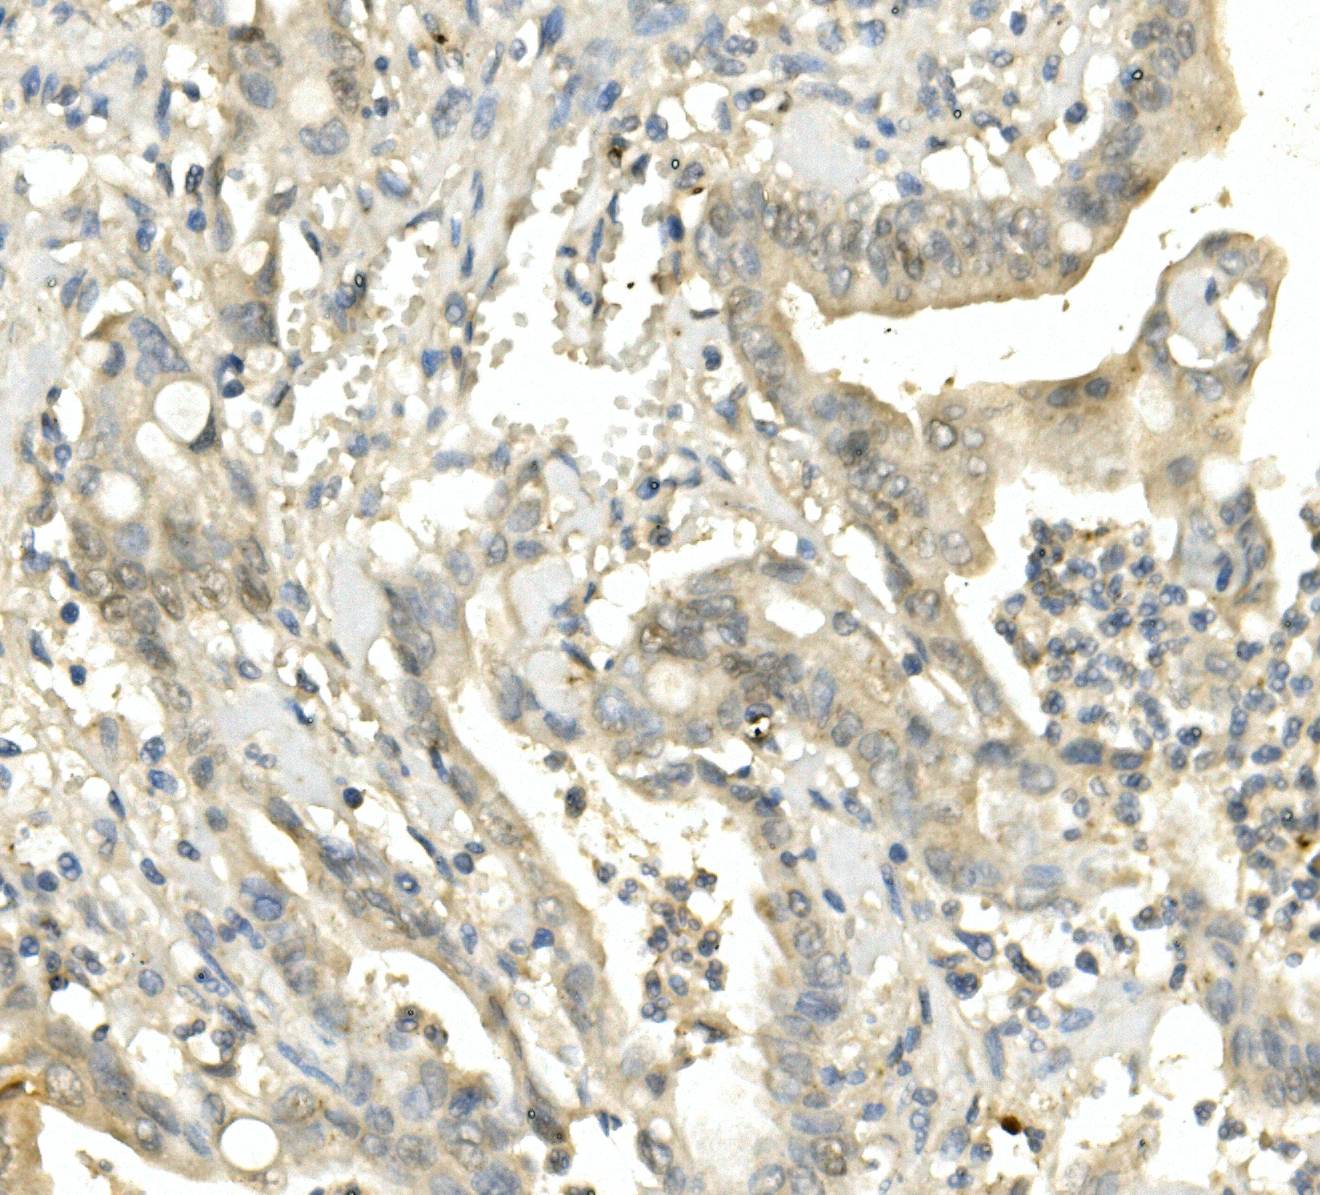

IHC analysis of BubR1/BUB1B using anti-BubR1/BUB1B antibody (M01564-3).

BubR1/BUB1B was detected in a paraffin-embedded section of human rectal cancer tissue. Biotinylated goat anti-mouse IgG was used as secondary antibody. The tissue section was incubated with mouse anti-BubR1/BUB1B Antibody (M01564-3) at a dilution of 1:200 and developed using Strepavidin-Biotin-Complex (SABC) (Catalog # SA1021) with DAB (Catalog # AR1027) as the chromogen.